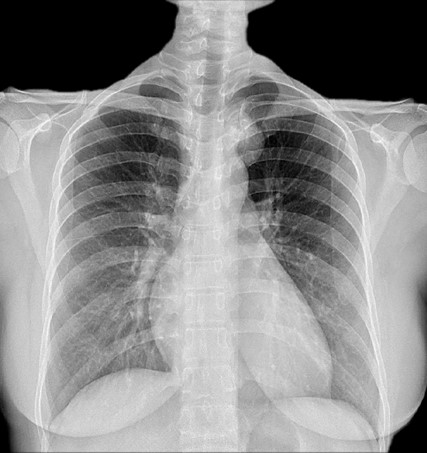

A 36-year-old female presented to our Neurosurgery outpatient department with complaints of upper to mid-back pain and left radiculopathy for the past 6 months. Patient had no obvious soft tissue swelling. No history of trauma, falls, or injuries to the back or spine. No complaints of fever, chills, unexplained weight loss, or night sweats. No weakness or paralysis in extremities. No cardiovascular symptoms (chest pain, shortness of breath). Chest X Ray (Fig. 1) was suggestive of a lobulated radio opaque shadow in the left paratracheal region at the level of T3-T4 vertebra.

Figure 1. Chest X ray PA view showing a homogenous, lobulated radio opacity seen in the left paratracheal region at the level of T3- T4 vertebrae.